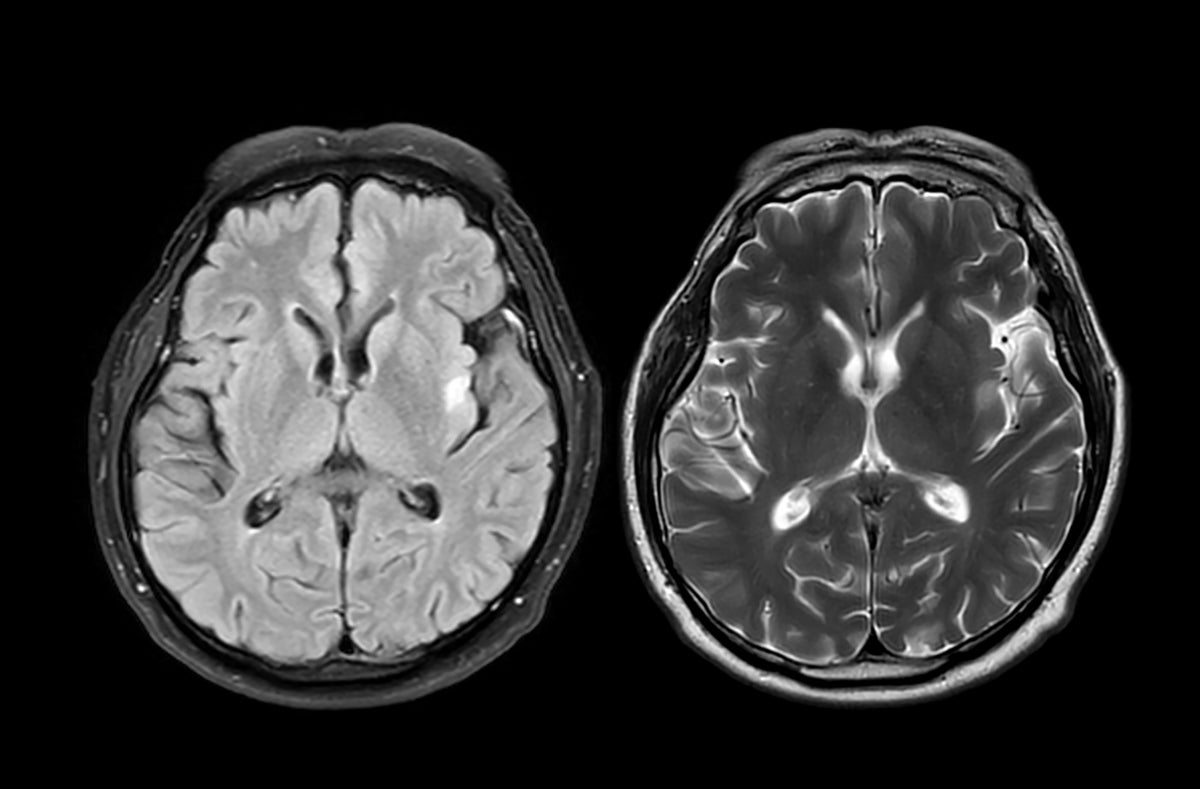

Researchers in the U.K. analyzed brain MRI scans from nearly 1,000 healthy adults taken before and during the COVID-19 pandemic using U.K. Biobank data. They trained a machine-learning model on hundreds of structural MRI features to estimate brain age. People who had scans during the pandemic showed accelerated brain aging, averaging about five and a half months older than prepandemic trends. The accelerated aging occurred even among individuals who did not contract COVID-19. Structural brain changes did not always coincide with cognitive decline; processing speed and problem-solving often remained unchanged in uninfected participants.